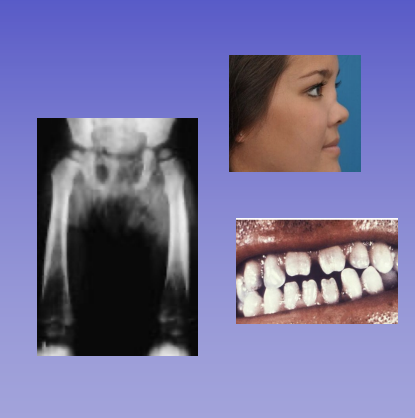

Congenital syphilis

• Manifestations